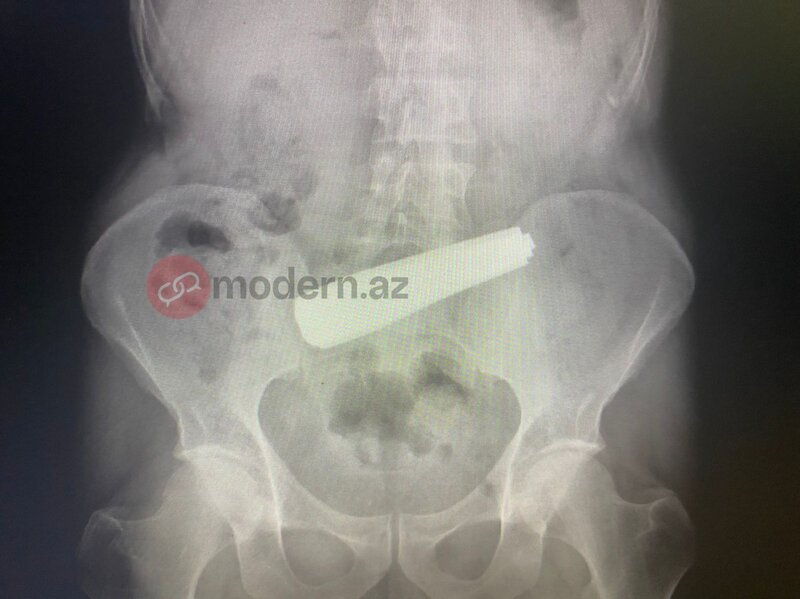

Bakıda bir nəfər 9 ədəd qaşıq uddu (FOTO)

Bakıda bir nəfər 9 ədəd qaşıq udub.

Nəhayət, Bakı Sağlamlıq Mərkəzinə çatdırılan pasiyentə dərhal tibbi müdaxilə olunub. Məlumata görə, xəstə 9 ədəd metal qaşığı udub. Həkimlər tərəfindən həyata keçirilən əməliyyat uğurla başa çatıb.